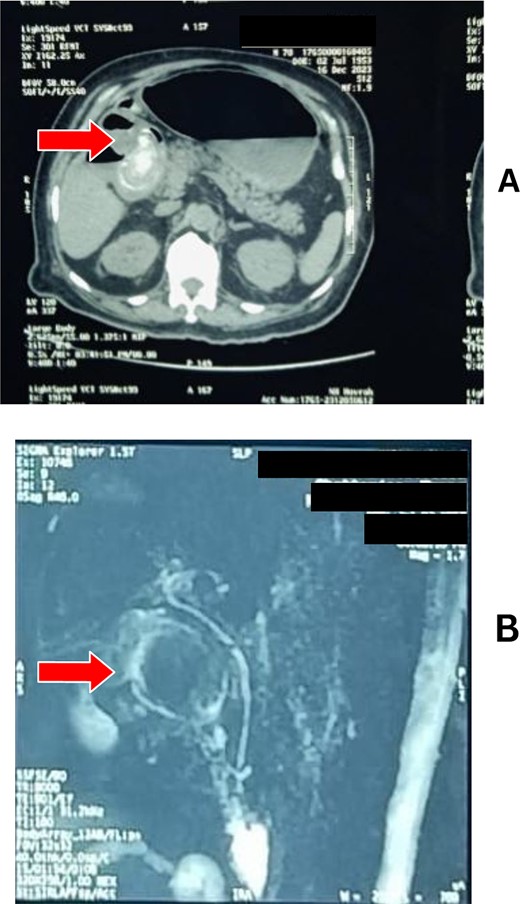

Abdominal sonography revealed a distended gall bladder filled with sludge and a grossly distended stomach. Upper GI endoscopy uncovered residual food, and a peeping gallstone impacted distal to the pyloric ring, indicating BS (Fig. 1). Endoscopic disimpaction was unsuccessful. Computed tomography and MR cholangiography confirmed a large gallstone, causing a cholecystoenteric fistula with significant inflammatory changes and gastric outlet obstruction (Fig. 2).

(A) CT scan and (B) MRCP showing a hugely distended stomach with a gallstone obstructing the pylorus.